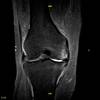

En nuestros centros se realizan estudios y diagnósticos de resonancia magnética musculo-esquelética

de Resonancia ,Magnética Musculo-Esquelética, de la marca italiana Esaote, es único en su diseño ya que nos permite realizar exámenes en bipedestación (el paciente estará de pie, para que se tenga otra perspectiva del comportamiento del cuerpo durante el examen).